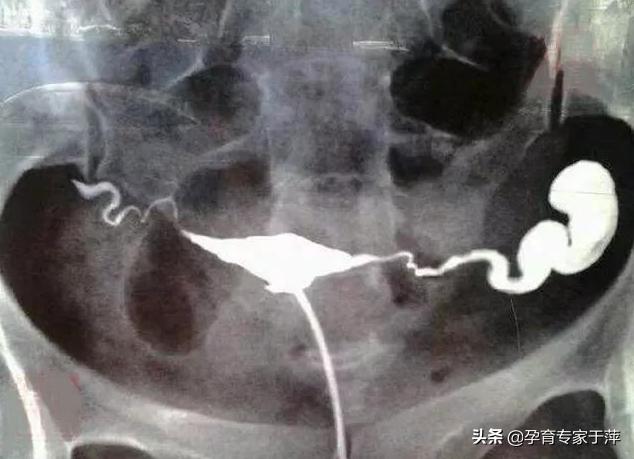

5、输卵管积水

造影片的表现是一侧或双侧输卵管远端增粗、膨大,呈“腊肠状”。这是由于输卵管远端粘连不通导致输卵管内造影剂不能溢出所导致。所以,输卵管积水的前提是输卵管不通。如果造影片显示输卵管伞端有造影剂溢出就不是积水。